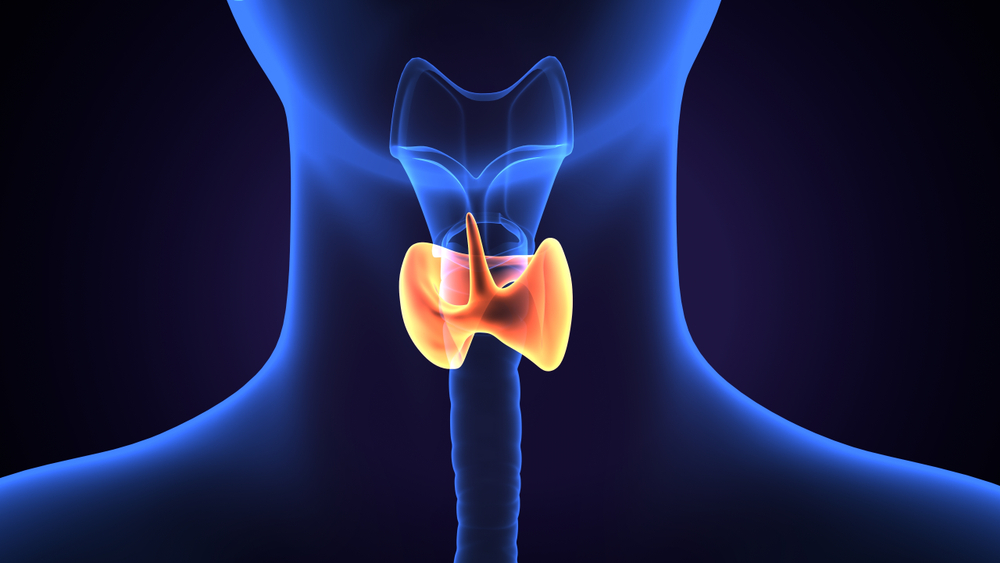

Chirurgia paratiroidiană este o procedură specializată destinată tratării afecțiunilor glandelor paratiroide, cel mai frecvent hiperparatiroidismul. Aceste glande mici, situate în apropierea tiroidei, au un rol esențial în reglarea nivelului de calciu din organism. Când una sau mai multe glande paratiroide devin hiperactive, pot determina creșterea nivelului de calciu în sânge, cauzând simptome precum dureri osoase, slăbiciune musculară, oboseală și pietre la rinichi.

Hiperparatiroidismul primar apare atunci când una sau mai multe glande paratiroide devin hiperactive din cauza unui adenom paratiroidian, o tumoră benignă care provoacă producția excesivă de hormon paratiroidian (PTH). Acest exces de PTH crește nivelul de calciu în sânge, cauzând simptome precum dureri osoase, slăbiciune musculară, oboseală, urinare frecventă, pietre la rinichi și tulburări cognitive. Deoarece nu există tratamente medicamentoase definitive pentru corectarea acestui dezechilibru hormonal, chirurgia este adesea necesară pentru a elimina glanda(le) afectate și a restabili echilibrul calciului.

Apare atunci când glandele paratiroide devin hiperactive ca răspuns la niveluri scăzute de calciu, adesea din cauza bolii cronice de rinichi sau altor afecțiuni care afectează metabolismul calciului și vitaminei D. Glandele produc excesiv hormon paratiroidian (PTH) pentru a restabili echilibrul calciului. Tratamentul principal presupune gestionarea cauzei subiacente și utilizarea medicamentelor sau suplimentelor pentru reglarea nivelurilor de calciu și fosfor. În cazurile în care aceste măsuri nu sunt suficiente, se poate lua în considerare intervenția chirurgicală, de obicei doar în cazuri severe sau persistente de hiperparatiroidism secundar, care provoacă simptome precum dureri osoase, fracturi sau calcificarea vaselor de sânge.

Apare de obicei la pacienții cu hiperparatiroidism secundar cronic, adesea din cauza bolii cronice de rinichi. Chiar și după tratarea afecțiunii subiacente (de exemplu, după un transplant renal), glandele paratiroide pot rămâne permanent hiperactive și pot continua să producă exces de hormon paratiroidian (PTH). Acest lucru duce la niveluri persistente ridicate de calciu, care pot provoca complicații precum dureri osoase, slăbiciune și probleme cardiovasculare. În cazurile de hiperparatiroidism terțiar, intervenția chirurgicală este recomandată de obicei pentru îndepărtarea glandelor hiperactive, restabilirea nivelurilor normale de calciu și ameliorarea simptomelor.

este o afecțiune rară, dar gravă, în care se formează o tumoră malignă într-una dintre glandele paratiroide. Acest tip de cancer poate determina creșterea semnificativă a nivelului de calciu în sânge, ducând la simptome severe, precum dureri osoase, slăbiciune musculară, oboseală și chiar complicații care pun viața în pericol, cum ar fi insuficiența renală sau probleme cardiovasculare. Chirurgia este tratamentul principal pentru cancerul paratiroidian și presupune îndepărtarea completă a glandei afectate, împreună cu țesuturile înconjurătoare, dacă este necesar, pentru a asigura excizia completă a tumorii și a preveni recidiva.

Pregătirea pentru chirurgia paratiroidiană implică analize detaliate de sânge pentru a măsura nivelurile de calciu și hormon paratiroidian (PTH). Studiile imagistice avansate ajută la localizarea glandelor afectate. Pot fi necesare ajustări ale medicației, iar instrucțiuni specifice vor fi oferite pentru a vă ajuta în pregătire.